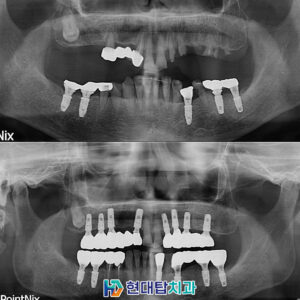

울산동구치과 안정적인 진료로 <목차> 서론 : 우리 치과에서 진행하는 수면치과치료의 장점 본론 : 치과 치료 증례 결론 : 치과 치료에 대한 구체적 안내   사람은 생후 6개월경에 첫 유치가 올라와 모두 한 번씩 빠지고 그 자리에 영구치가 올라옵니다. ​ 영구치는 한 번 올라오고 난 후에는 평생을 걸쳐 사용하게 됩니다. ​ 더보기…

울산동구치과 망설이고 있다면 임플란트의 정의 실제 임플란트 사례 상악동 & 의식하 진정 임플란트란 의료진 소개 치아 건강은 백세 시대 속에서 삶의 질을 결정하는 핵심 요소입니다. ​ 치아는 음식물을 저작하고 부수는 저작활동을 하면서 원활한 소화가 이루어질 수 있도록 도움을 줍니다. ​ 하지만 한번 손상되거나 상실된 치아는 회복이 불가능하기 때문에 정기적인 치과검진과 더보기…